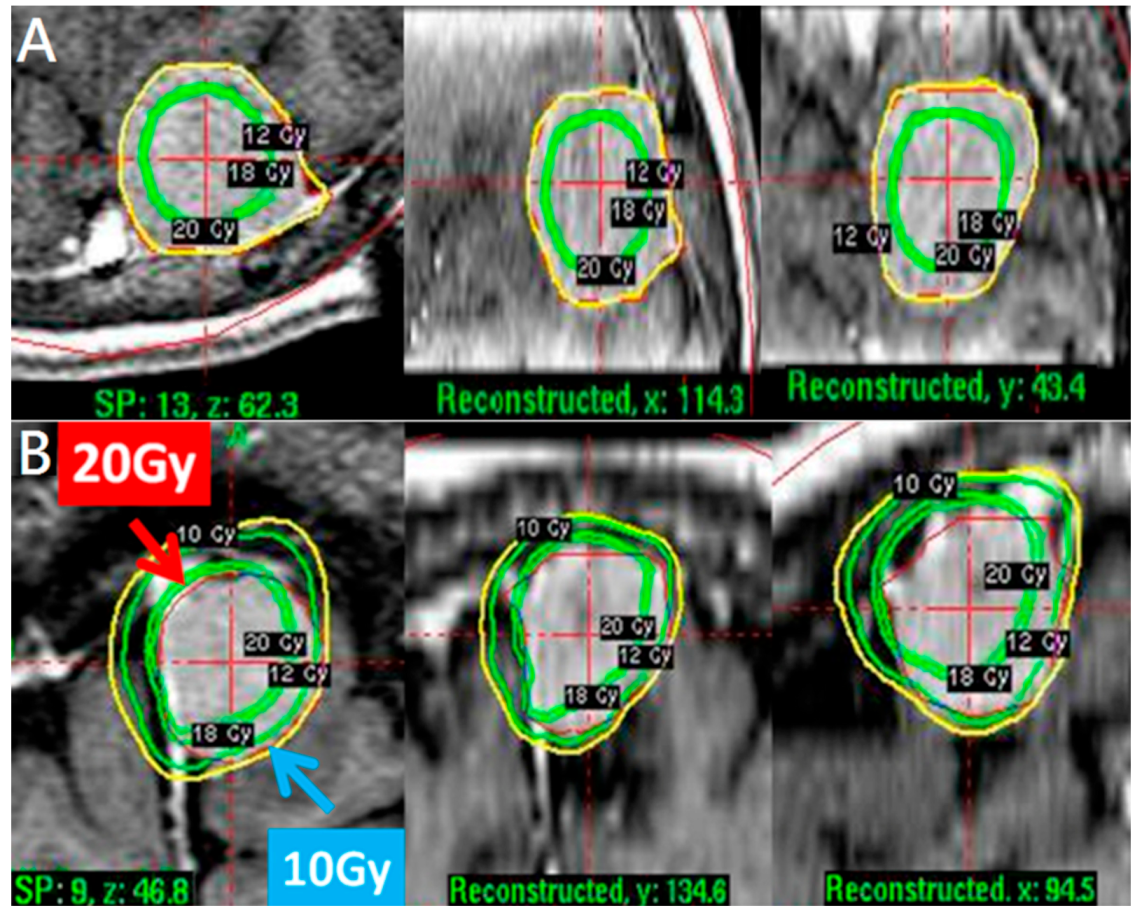

2.2. Treatment Approach and Exposure Variable